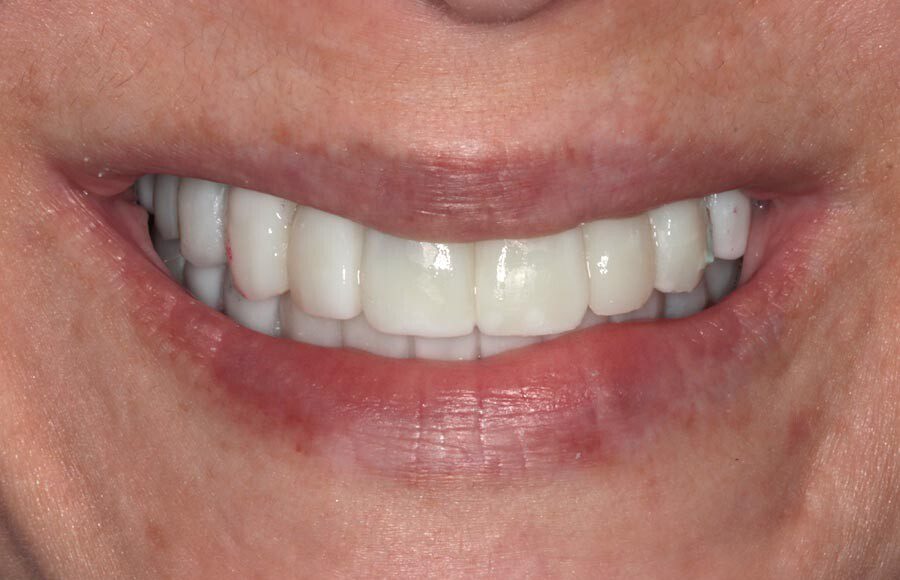

The definitive bridges are delivered, the bite is verified, and the screws are torqued down firmly. The final result is strong, functional, and esthetic restorations that will serve the patient well for years to come.

The patient couldn’t be happier with her new smile. We have improved not only her esthetics but her oral health as well. She now has beautiful restorations she can keep for years to come. Contact us if you would like to have a consultation and see if this is the right treatment for you!